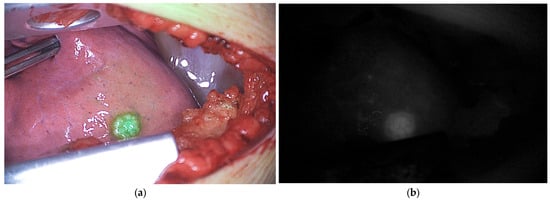

- Richard, C.; White, S.; Williams, R.; Zaghloul, T.; Helmig, S.; Sheyn, A.; Abramson, Z.; Abdelhafeez, H. Indocyanine Green near Infrared-Guided Surgery in Children, Adolescents, and Young Adults with Otolaryngologic Malignancies. Auris Nasus Larynx 2023, 50, 576–585. [Google Scholar] [CrossRef]

| Clinical | Pediatric | Otolaryngologic malignancies | Tumor extension | ICG 1.5 mg/kg 24 h before surgery | [43] | |